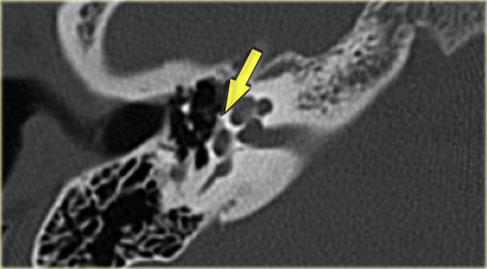

Bên trái là hình ảnh của một bệnh nhân nam 58 tuổi.

Mũi tên màu xanh chỉ cống ốc tai đi về phía ốc tai.

Hình ảnh này có thể bị nhầm lẫn với đường gãy xương (mũi tên).

Lưu ý có hình ảnh mờ đục của hòm nhĩ và các tế bào khí xương chũm.